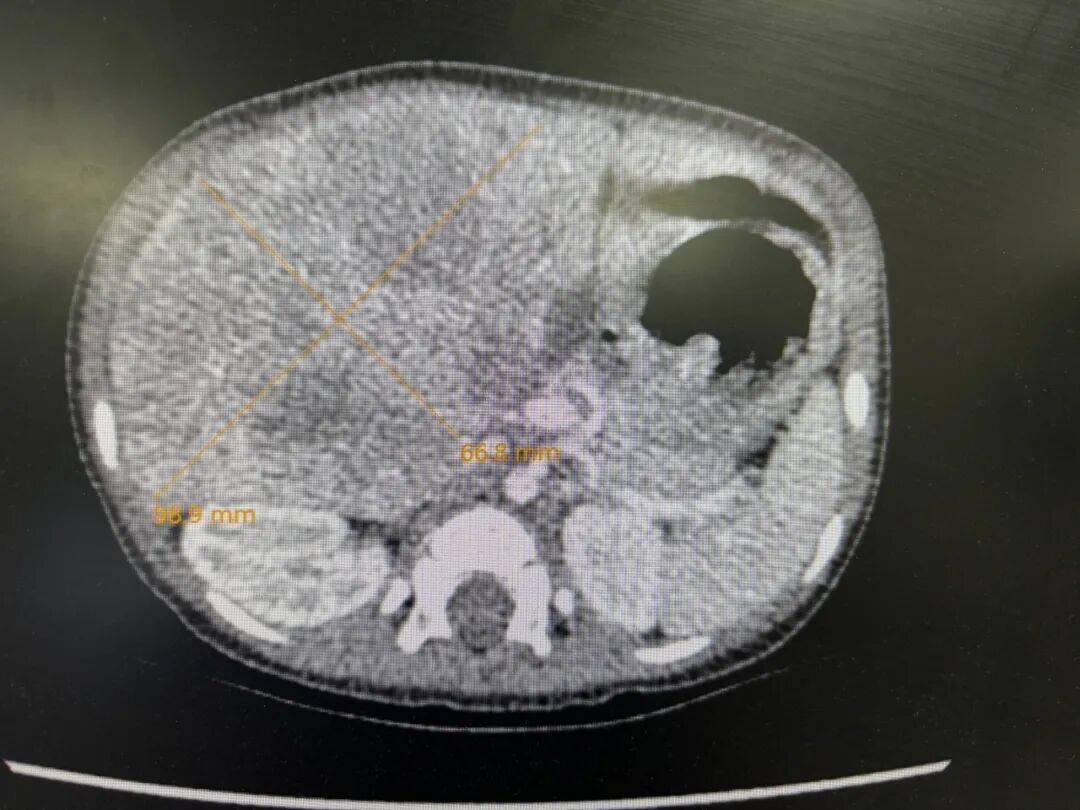

于是,爸爸妈妈带着妍妍找到武玉睿主任,在完善了各项检查后,基本可以明确,是肝母细胞瘤,最大径线达8厘米。肿瘤主要侵犯了肝第5段,6段和7、8段也有部分侵犯,肿瘤不止严重压迫正常肝组织和周围脏器,还与肝内的主要Glisson系统和肝静脉系统分界不清,如果贸然手术,要么需要扩大切除,这样就会丢失更多的肝组织;要么就不容易切干净肿瘤,因为初发肿瘤往往与肝内管道界限不清,强行手术的话肝内管道壁上容易残存瘤细胞,而且在肿瘤周围还有可能存在检查不出来的微小卫星灶,这都会增加术后复发的风险。经过权衡,武玉睿主任建议先给妍妍穿刺活检后做化疗,这样既可使瘤体缩小,又能使肿瘤建立假包膜,下次手术的时候,肿瘤与正常组织之间会有一个潜在间隙。而且化疗后,肿瘤周围可能存在的微小卫星灶一般也就被消灭掉了,所以化疗后再手术,肿瘤切除应该更彻底,复发率更低。经过了三轮的新辅助化疗,妍妍肝脏上的肿瘤比之前小了不少,于是,武玉睿主任决定给妍妍做根治手术。

化疗后